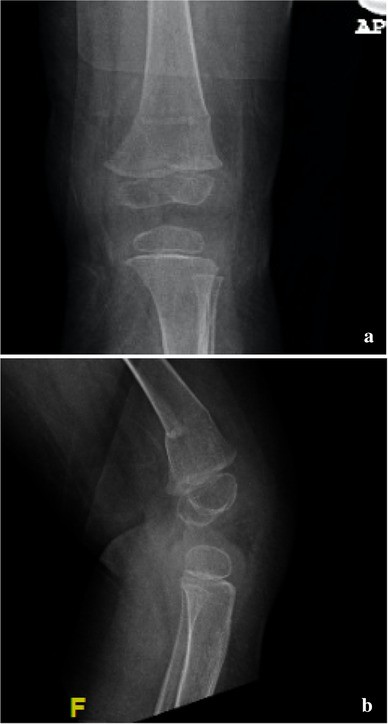

Fig. 3

a Anteroposterior and b lateral femur radiographs showing osteoporotic fracture after casting, following ipsilateral open reduction